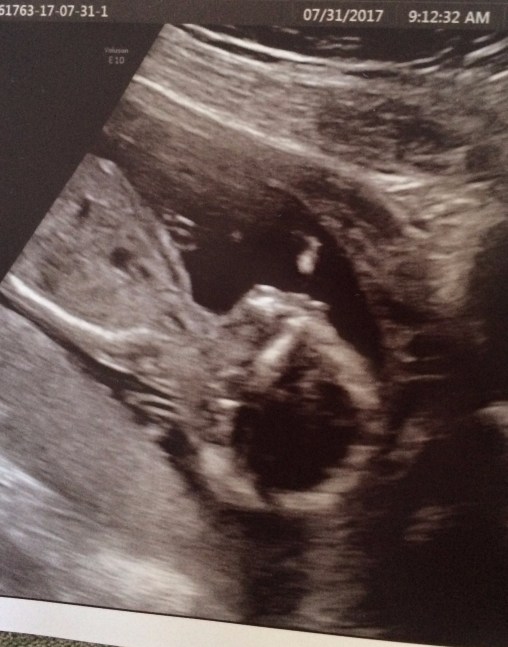

I received permission to post the first picture of the new GRANDBABY!!